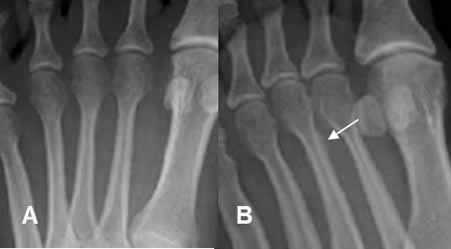

Fig 7. Luxación de los dedos.

A: Rx AP del 5º dedo. No se aprecian anormalidades.

B: Rx lateral del 5º dedo. Luxación posterior de la articulación interfalángica distal.